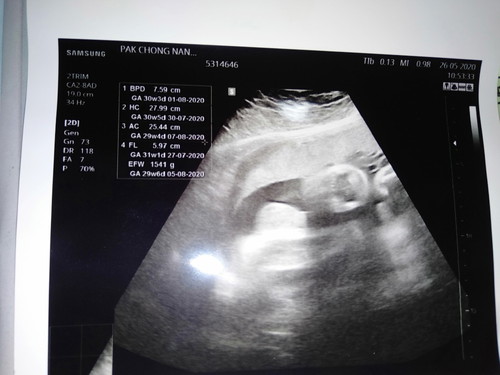

32+1 แต่น้องนน.น้อยไม่ตามเกณฑ์

วันนี้ 25/05/63 ครบ 32+1 ค่ะ ไปหาหมอ ซาวด์ดูน้องและตรวจปากมดลูกค่ะเพราะเคยท้องปั้นแข็งต้องแอดมิดที่ รพ.ตอน 28+3 ค่ะ น้องนน.น้อยกว่าเกณฑ์เกือบทุกอย่างเลยค่ะ ตามในใบซาวด์เลยค่ะ เพิ่มนน.น้องยังไงดีค่ะให้ออกมาไม่แพ้อาหารชนิดนั้นค่ะ อีก 2 อาทิตย์ หมอนัดอีกรอบ